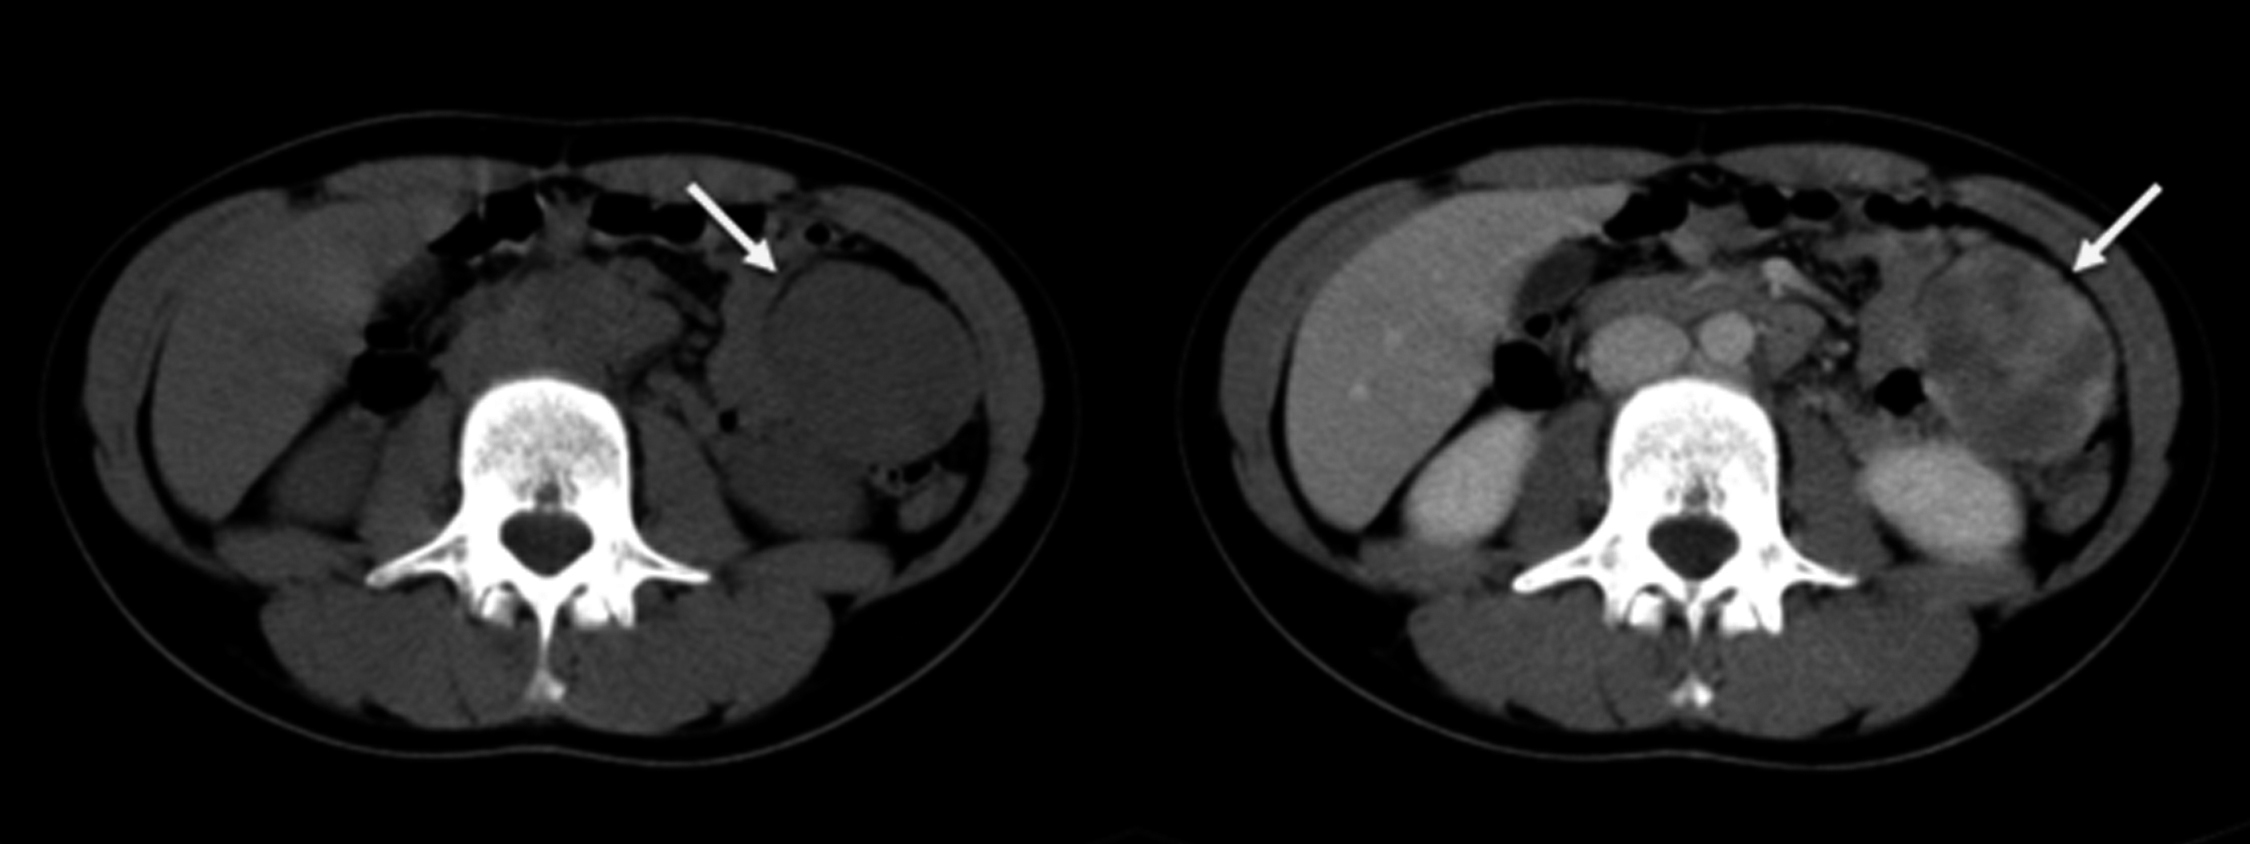

Se realiza TC de abdomen y pelvis sin y con medio de contraste intravenoso. Se identifica a nivel de flanco izquierdo masa sólida, bilobulada, de bordes lisos, bien definida, que mide 80 x 50 x 50 mm de diámetro en sus ejes L, T, AP respectivamente, con realce heterogéneo con el medio de contraste. Se encuentra por delante del colon descendente y por fuera de las asas delgadas e impresiona tener plano de separación con dichas estructuras, por lo que se interpreta que probablemente corresponda a una masa intraperitoneal (Figura 6).

Figura 6

TC de abdomen: corte axial previo al contraste donde se evidencia a nivel del flanco izquierdo masa sólida bilobulada con bordes lisos (a), que muestra realce heterogéneo luego de la administración de contraste (b) (flechas)

Varios meses después la paciente consulta por cuadro de dolor abdominal tipo cólico, acompañado de náuseas y vómitos de una semana de evolución. Al examen físico se destaca abdomen levemente distendido, blando, depresible con dolor a la palpación centroabdominal, sin defensa. Se solicitan rutinas de laboratorio y ecografía abdominal que no presentan alteraciones.

Se realiza otra TC de abdomen y pelvis, sin y con medio de contraste intravenoso. Se identifica masa sólida de similares características que en la TC previa, pero actualmente localizada en hipocondrio izquierdo, subhepática, adyacente a la curvatura gástrica mayor y asas delgadas. Se observan asas delgadas distendidas con niveles hidroaéreos, con zona de transición a nivel pelviano. Se plantea oclusión por bridas. (Figura 7)

Los cambios en la localización de la masa nos advierten de su relación con alguna estructura móvil del abdomen, en este caso el mesenterio, razón por la cual no fue ubicada en la primera intervención quirúrgica.